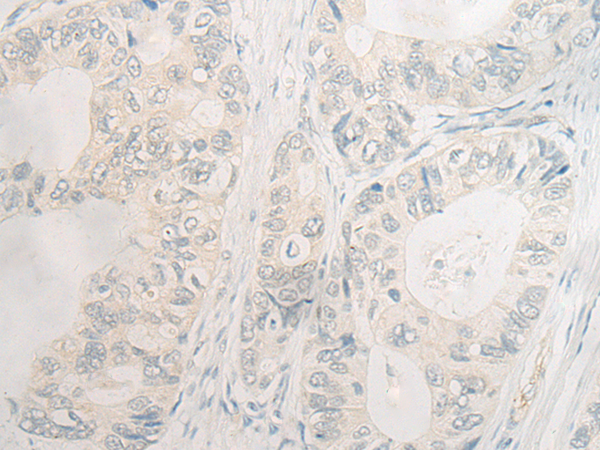

分类: 科研抗体货号: P06410别名: EDEM应用: IHC反应种属: Human, Mouse